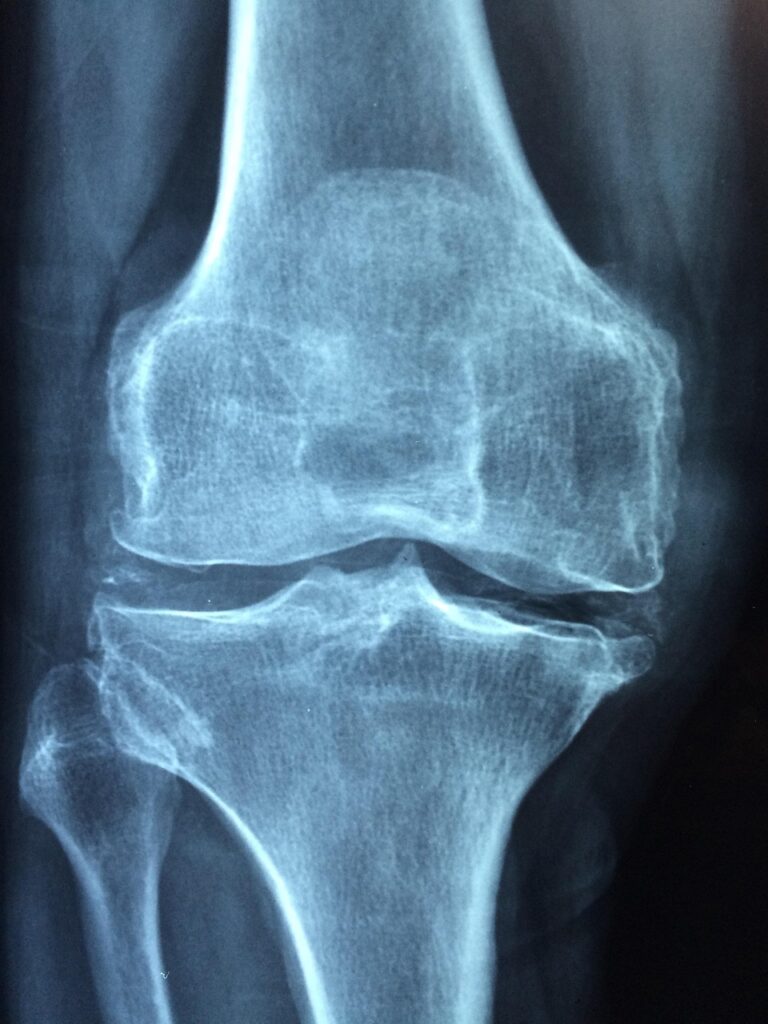

膝手術後の痛みはいつまで続くのか?

膝手術を受けた後、痛みが続くことに不安を感じる方は多いですよね。特に、どれくらいの期間痛みが続くのか、そしてその痛みをどのように軽減することができるのかを知りたいと思うのは当然のことです。

手術後の痛みは、個々の体調や手術の内容によって異なるため、明確な答えを示すことは難しいです。しかし、一般的な目安や対処法についてお話ししますね。